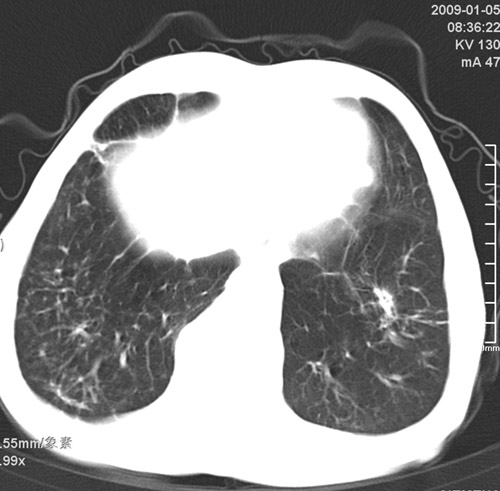

标题: CT17529:男 76 胸背部不适半月 胸透支气管炎 行CT检查 [打印本页]

标题: CT17529:男 76 胸背部不适半月 胸透支气管炎 行CT检查

意见 老年肺 少许炎症 肺大泡 右肺门略大 但支气管通畅  请各位高手指教如何下意见

间质纤维化伴少许炎症!另:肺大泡形成!

慢支肺气肿,肺动脉高压.